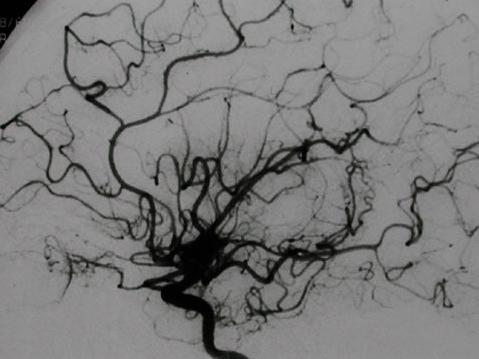

浩浩,今年5岁,忽然出现偏瘫,表现为右边的手和脚都不能活动,家长连忙送到医院诊治。接诊时,我思考这孩子的症状类似大人脑卒中的症状,会不会是脑出血或者脑梗塞?于是,我帮他检查了脑部磁共振的血管造影,发现脑部密集的小血管就像吸烟时吐出的烟雾。看到这个影像学的检查资料,我考虑浩浩得了“小儿烟雾病”。

小儿烟雾病是以双侧颈内动脉末端进行性狭窄或闭塞,颅底异常血管网形成为特征的一组脑血管病。因为在影像学检查中,异常的血管网像吸烟时喷出来的烟雾而得名。这种病多发生在1岁3个月 ~12岁, 其中4~10岁占82.4%。

小儿烟雾病主要的确诊手段是影像学检查。目前,我们可以做脑血管造影和数字减影血管造影(DSA),还有磁共振的血管造影(MRA)来观察患儿的脑部血管分布,从而确诊此病。脑血管造影对烟雾病的诊断有重要价值,但传统的脑血管造影或 DSA 由于受年龄、创伤性等条件的限制,很难在儿科临床广泛应用。MRA 作为一种新的血管成像技术,能较好地反映颅内血管病变部位和范围,并且因其无创性、快捷、不需造影剂等特点,相对于脑血管造影或 DSA 来说,更适合应用于诊断小儿烟雾病。

最后,本病患儿的头痛要和儿童偏头痛相区别。偏头痛在脑部血管造影检查中,偏头痛多数在休息后,症状可缓解,脑部并无异常血管网形成,而小儿烟雾病的患儿脑部可见明显的异常血管网。